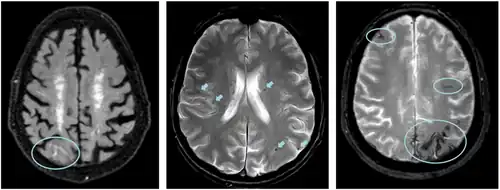

Left: ARIA-E with sulcal effusion (FLAIR sequence)

Middle: ARIA-H with multiple microbleeds (T2* weighted)

Right: ARIA-H with superficial siderosis (T2* weighted)

Two non-exclusive mechanisms have been postulated. Firstly, in the context of aging and neurodegeneration, the integrity of the blood-brain barrier (BBB) can become compromised, resulting in increased permeability. Notably, amyloid plaques have been hypothesized to counteract this BBB leakage.[7] However, upon the administration of antibodies, these plaques are targeted and subsequently eliminated, potentially uncovering the occurrence of micro-hemorrhage [8][9] Secondly, an alternate perspective posits that the introduction of antibodies into the bloodstream triggers an immune-inflammatory response as part of the treatment regimen. This orchestrated immune reaction might inadvertently precipitate micro-hemorrhages.[10]